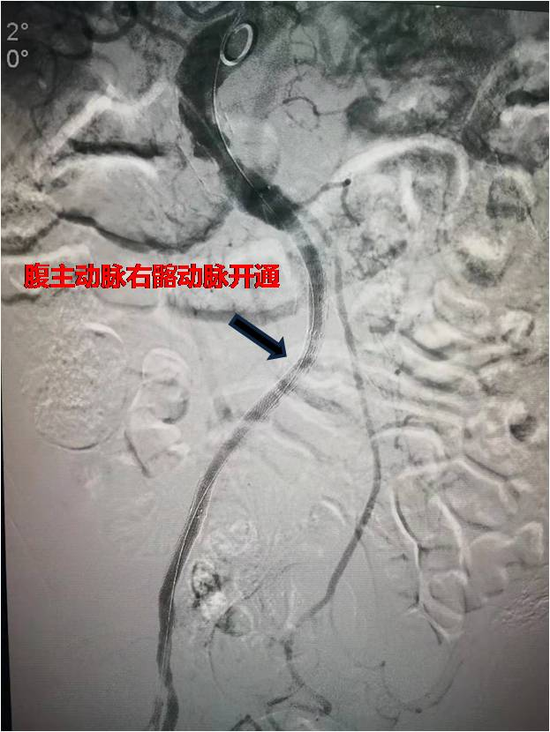

此次,超高龄复杂主髂动脉闭塞患者的成功救治,标志着西安交大一附在

图片尺寸550x732

团队再次研讨商定后,决定先行右侧髂内动脉弹簧栓塞治疗后,再行腹主

图片尺寸640x699